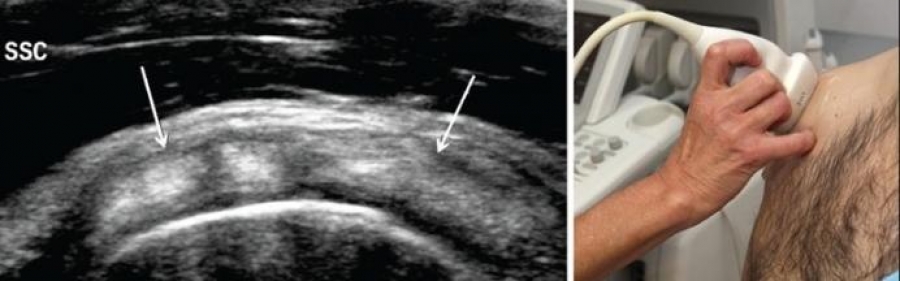

Una mala curación de la lesión puede provocar que se cronifique e imposibilite la práctica deportiva. Por eso es importante detectar los síntomas y aplicar el tratamiento lo antes posible. El diagnóstico mediante pruebas de imagen puede ayudarnos a determinar el tipo de lesión, pero siempre y cuando este asociado a una correcta evaluación de la sintomatología del paciente; puesto que una alteración estructural es tan solo un factor de riesgo para el desarrollo de patología.

Como en otras lesiones que afectan al tendón, es muy importante realizar una adecuada modulación de la carga según la fase evolutiva en la que se encuentre la lesión. Tras el examen y evaluación por parte del fisioterapeuta, se pueden aplicar diversas técnicas que influyan directamente en el tejido dañado, en este caso, del tendón del supraespinoso destinadas a recuperar la movilidad y que el paciente no sienta dolor. Técnicas como la EPTE con ecografia. Y los trabajos de hombro especificos, de la cual en Centro de fisioterapia Osteopatía y Acupuntura de Benahadux esta especializado en tratamiento de lesiones deportivas hacen que la recuperación sea mas rápida y efectiva.